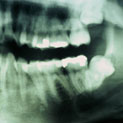

Aunque su estirpe anatomopatológica sea benigna, son quistes que en algunos pacientes provocan grandes destrucciones maxilares, porque crecen de forma asintomática durante años.

Su cirugía es sencilla y está basada en la extracción del quiste con criterios conservadores, y en la reconstrucción del defecto creado por la limpieza quirúrgica.

Para la reconstrucción, aconsejamos hacerlo en la misma intervención y con las bases de ingeniería tisular de la regeneración ósea guiada. Utilizamos como material óseo inductor el fosfato tricálcico tipo beta, mezclado con sangre del paciente y protegido con membrana de regeneración reabsorbible.